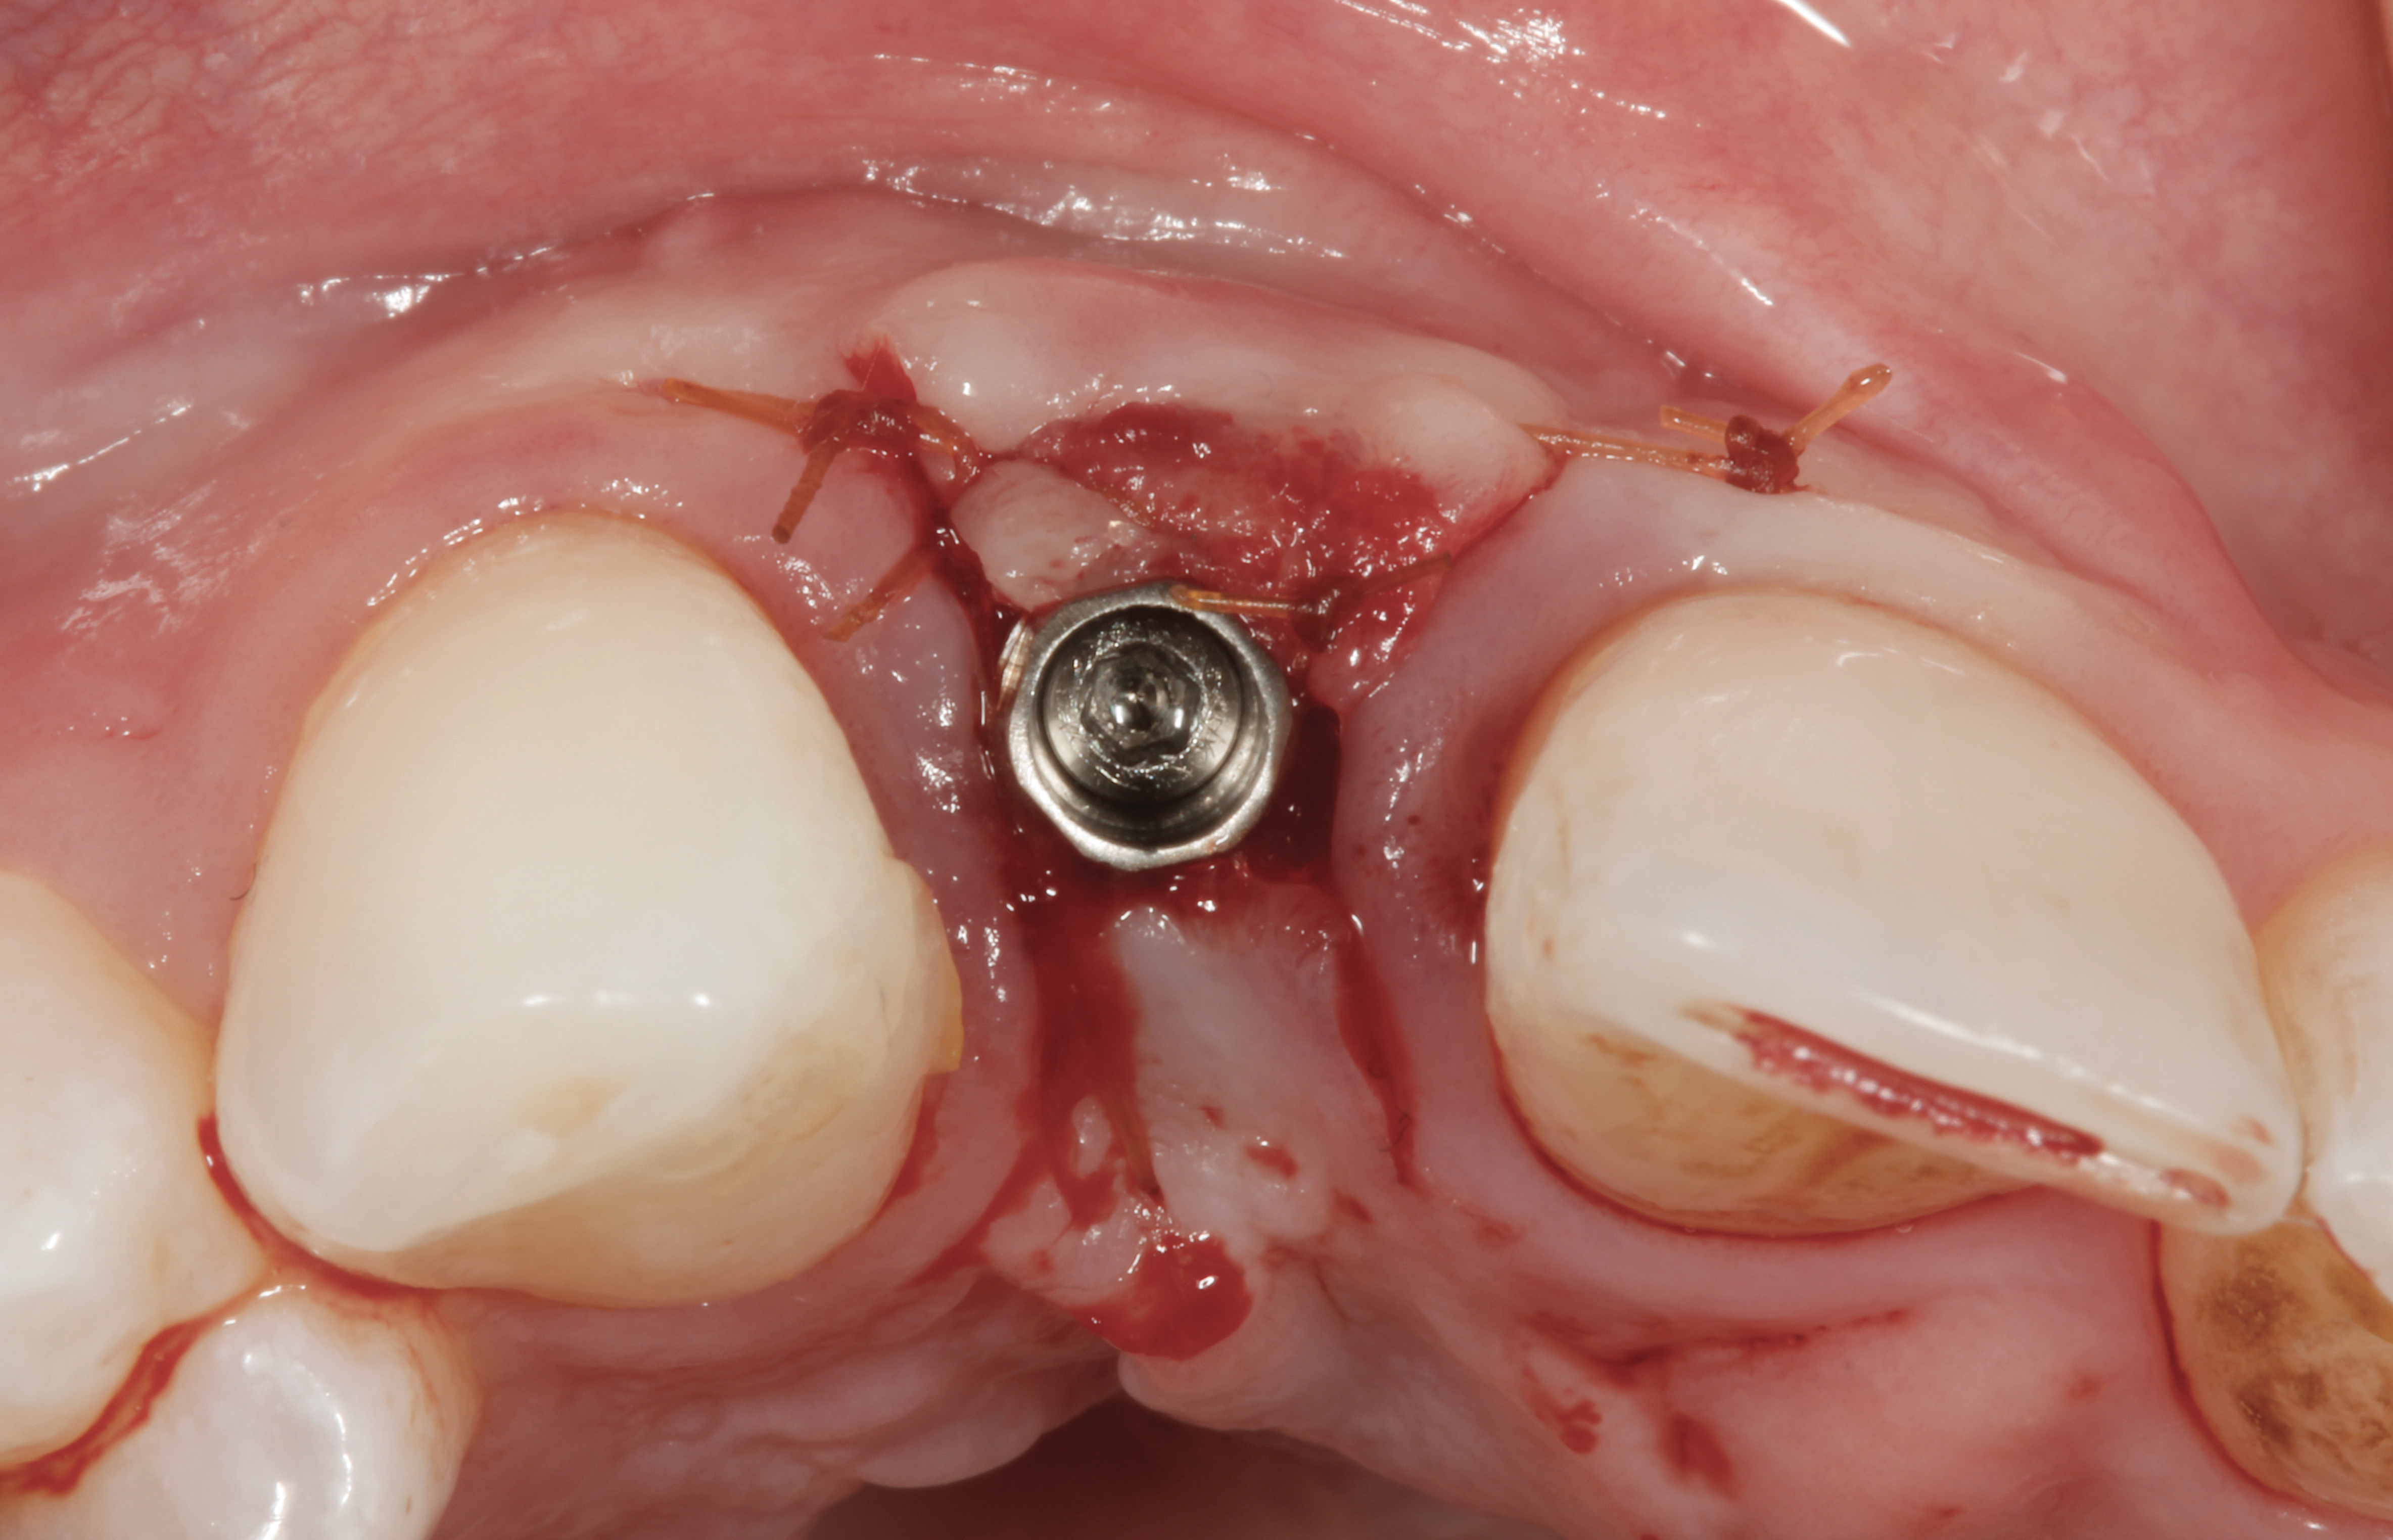

The crown and screw-retained custom abutment were removed, and a surgical cover screw was placed into the implant, thereby allowing spontaneous gingival augmentation in situ (Figure 33 and Figure 34). Note that the lingual aspect of the implant site was significantly more coronal than the labial aspect, which was positive because the defect would be limited to a facial–lingual defect. A fixed RBR bridge was cemented on the adjacent teeth and used as a tooth-supported transitional provisional restoration (Figure 35). A few weeks were allotted to let the soft tissue heal and migrate around the cover screw (Figure 36) to see if there would be complete coverage, thereby allowing a soft-tissue augmentation procedure to be performed with primary flap closure as in clinical scenario No. 2. The major obstacle in achieving a positive tissue response was that the implant depth was also deficient because the implant–abutment connection was at the level of the free gingival margin. It was decided that the best treatment option would be to remove the implant. A high-powered reverse-torque device (Fixture Remover Kit, NeoBiotech, www.neobiotechus.com) was used to remove the implant atraumatically (Figure 38 through Figure 41). The implant socket was allowed to heal for several months not unlike an extracted tooth (Figure 42). A new implant was placed in a better position from both a restorative and esthetic perspective (Figure 43), and after a few months of healing, a new crown was made (Figure 44). A satisfactory functional and esthetic result was achieved (Figure 45 and Figure 46) without employing pink porcelain.

Fig 38. A reverse-torque screw was placed into the implant.

Figure 38

Fig 39. A counter-torque device was placed over the reverse-torque screw.

Figure 39

Fig 40. The implant was easily unscrewed within minutes in a minimally invasive manner with less trauma to the surgical site.

Figure 40